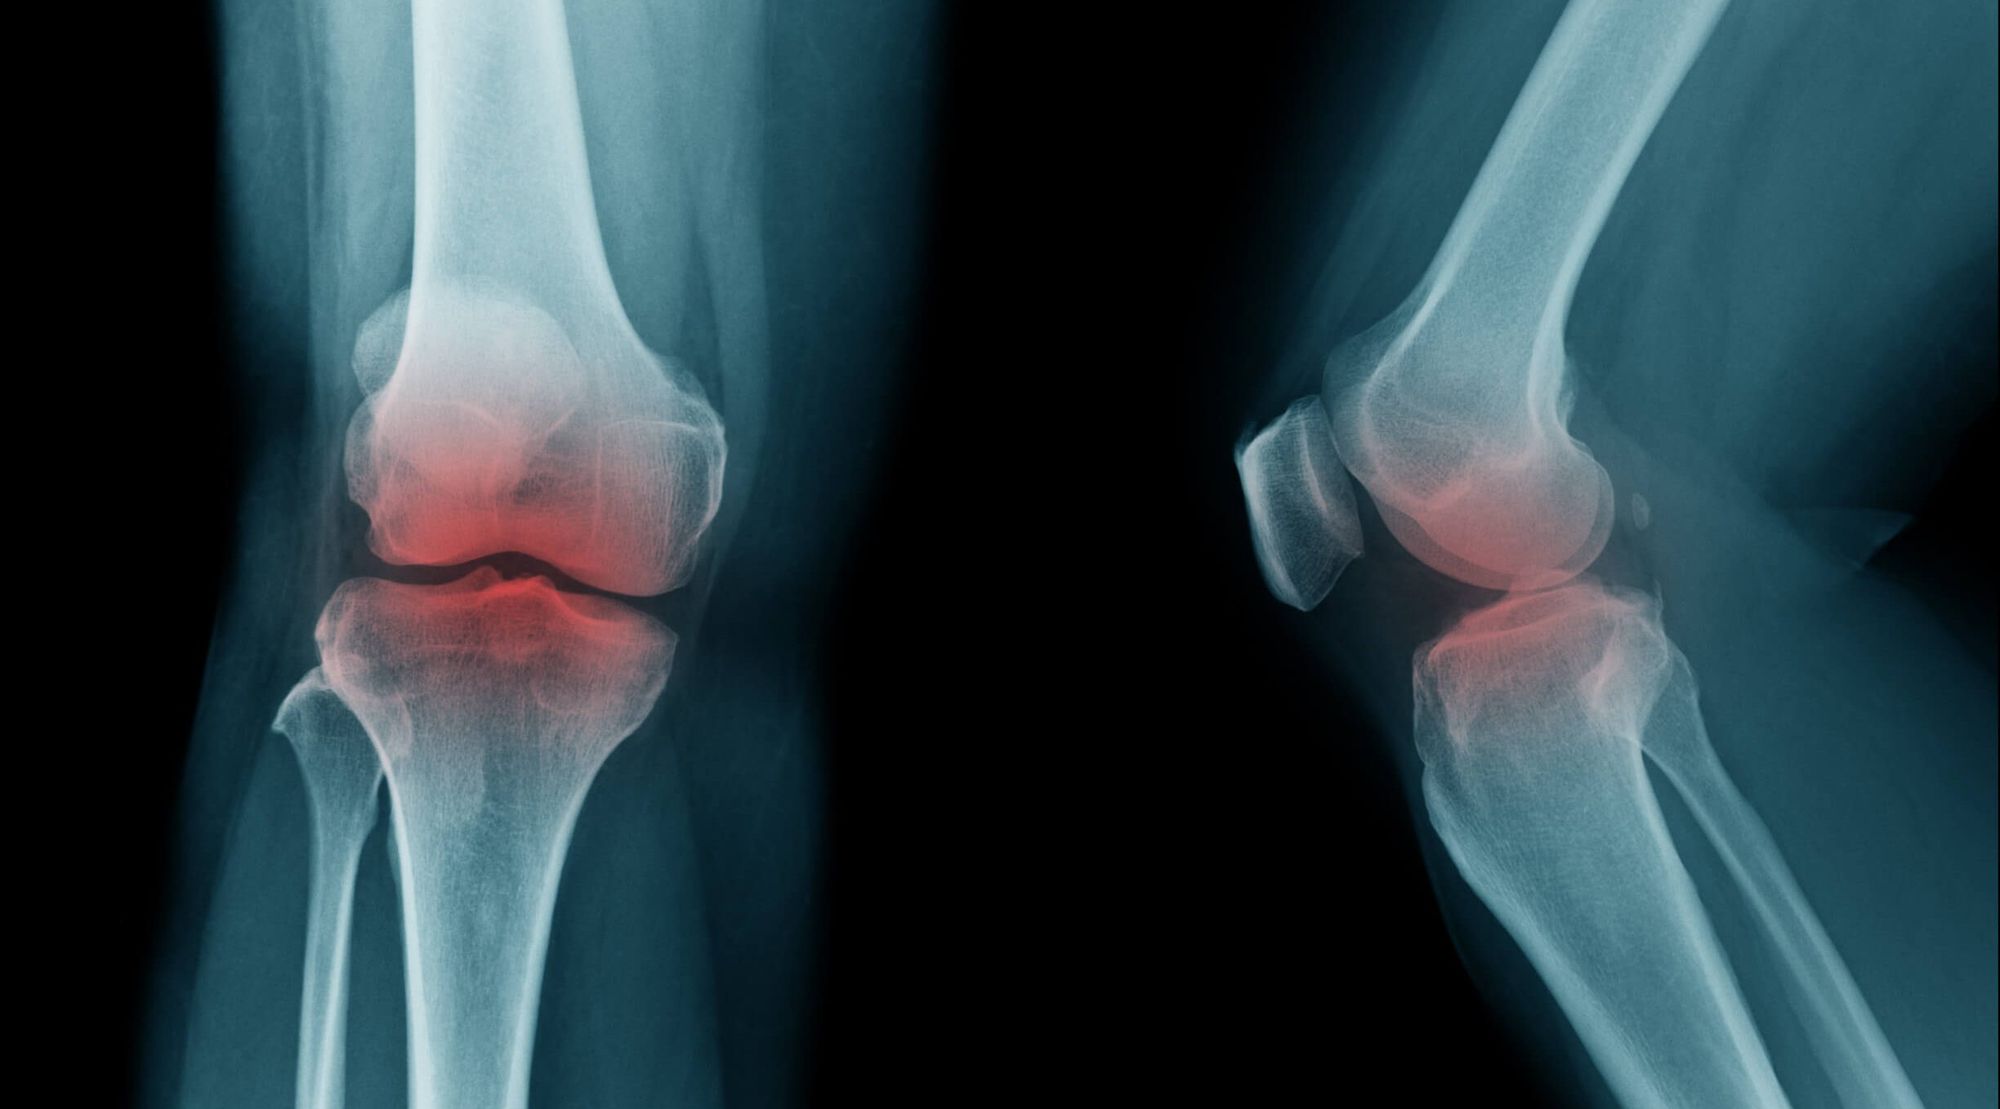

Challenge: Early-stage OA signs are invisible on plain X-rays, as cartilage degeneration cannot be directly assessed, and OA constitutes a three-dimensional problem. This is reflected by fair to moderate interobserver reliability for knee OA assessment using X-rays alone. To overcome these issues, different solutions, including novel quantitative grading methods as well as automatic knee X-ray assessment tools, have been proposed. Artificial intelligence (AI) and deep learning have been used in medical image classification related to the musculoskeletal system. The researchers analyzed the intra- and interobserver reliability of board-certified orthopedic surgeons (also known as senior readers) for knee OA grade assessment using either AI-annotated or plain X-rays. Afterwards, they compared the outcome of senior readers to that of senior residents (termed junior readers) with aided analysis in terms of agreement rate and overall performance.

Findings: The use of AI-based software leads to improvement in the radiological judgement of senior orthopedic surgeons with regard to X-ray features indicative of knee OA and KL grade, as measured by the agreement rate and overall accuracy in comparison to the ground truth. The agreement and accuracy rates of senior readers were comparable to those of junior readers with aided analysis. Consequently, standard of care may be improved by the additional application of AI-based software in the radiological evaluation of knee OA.